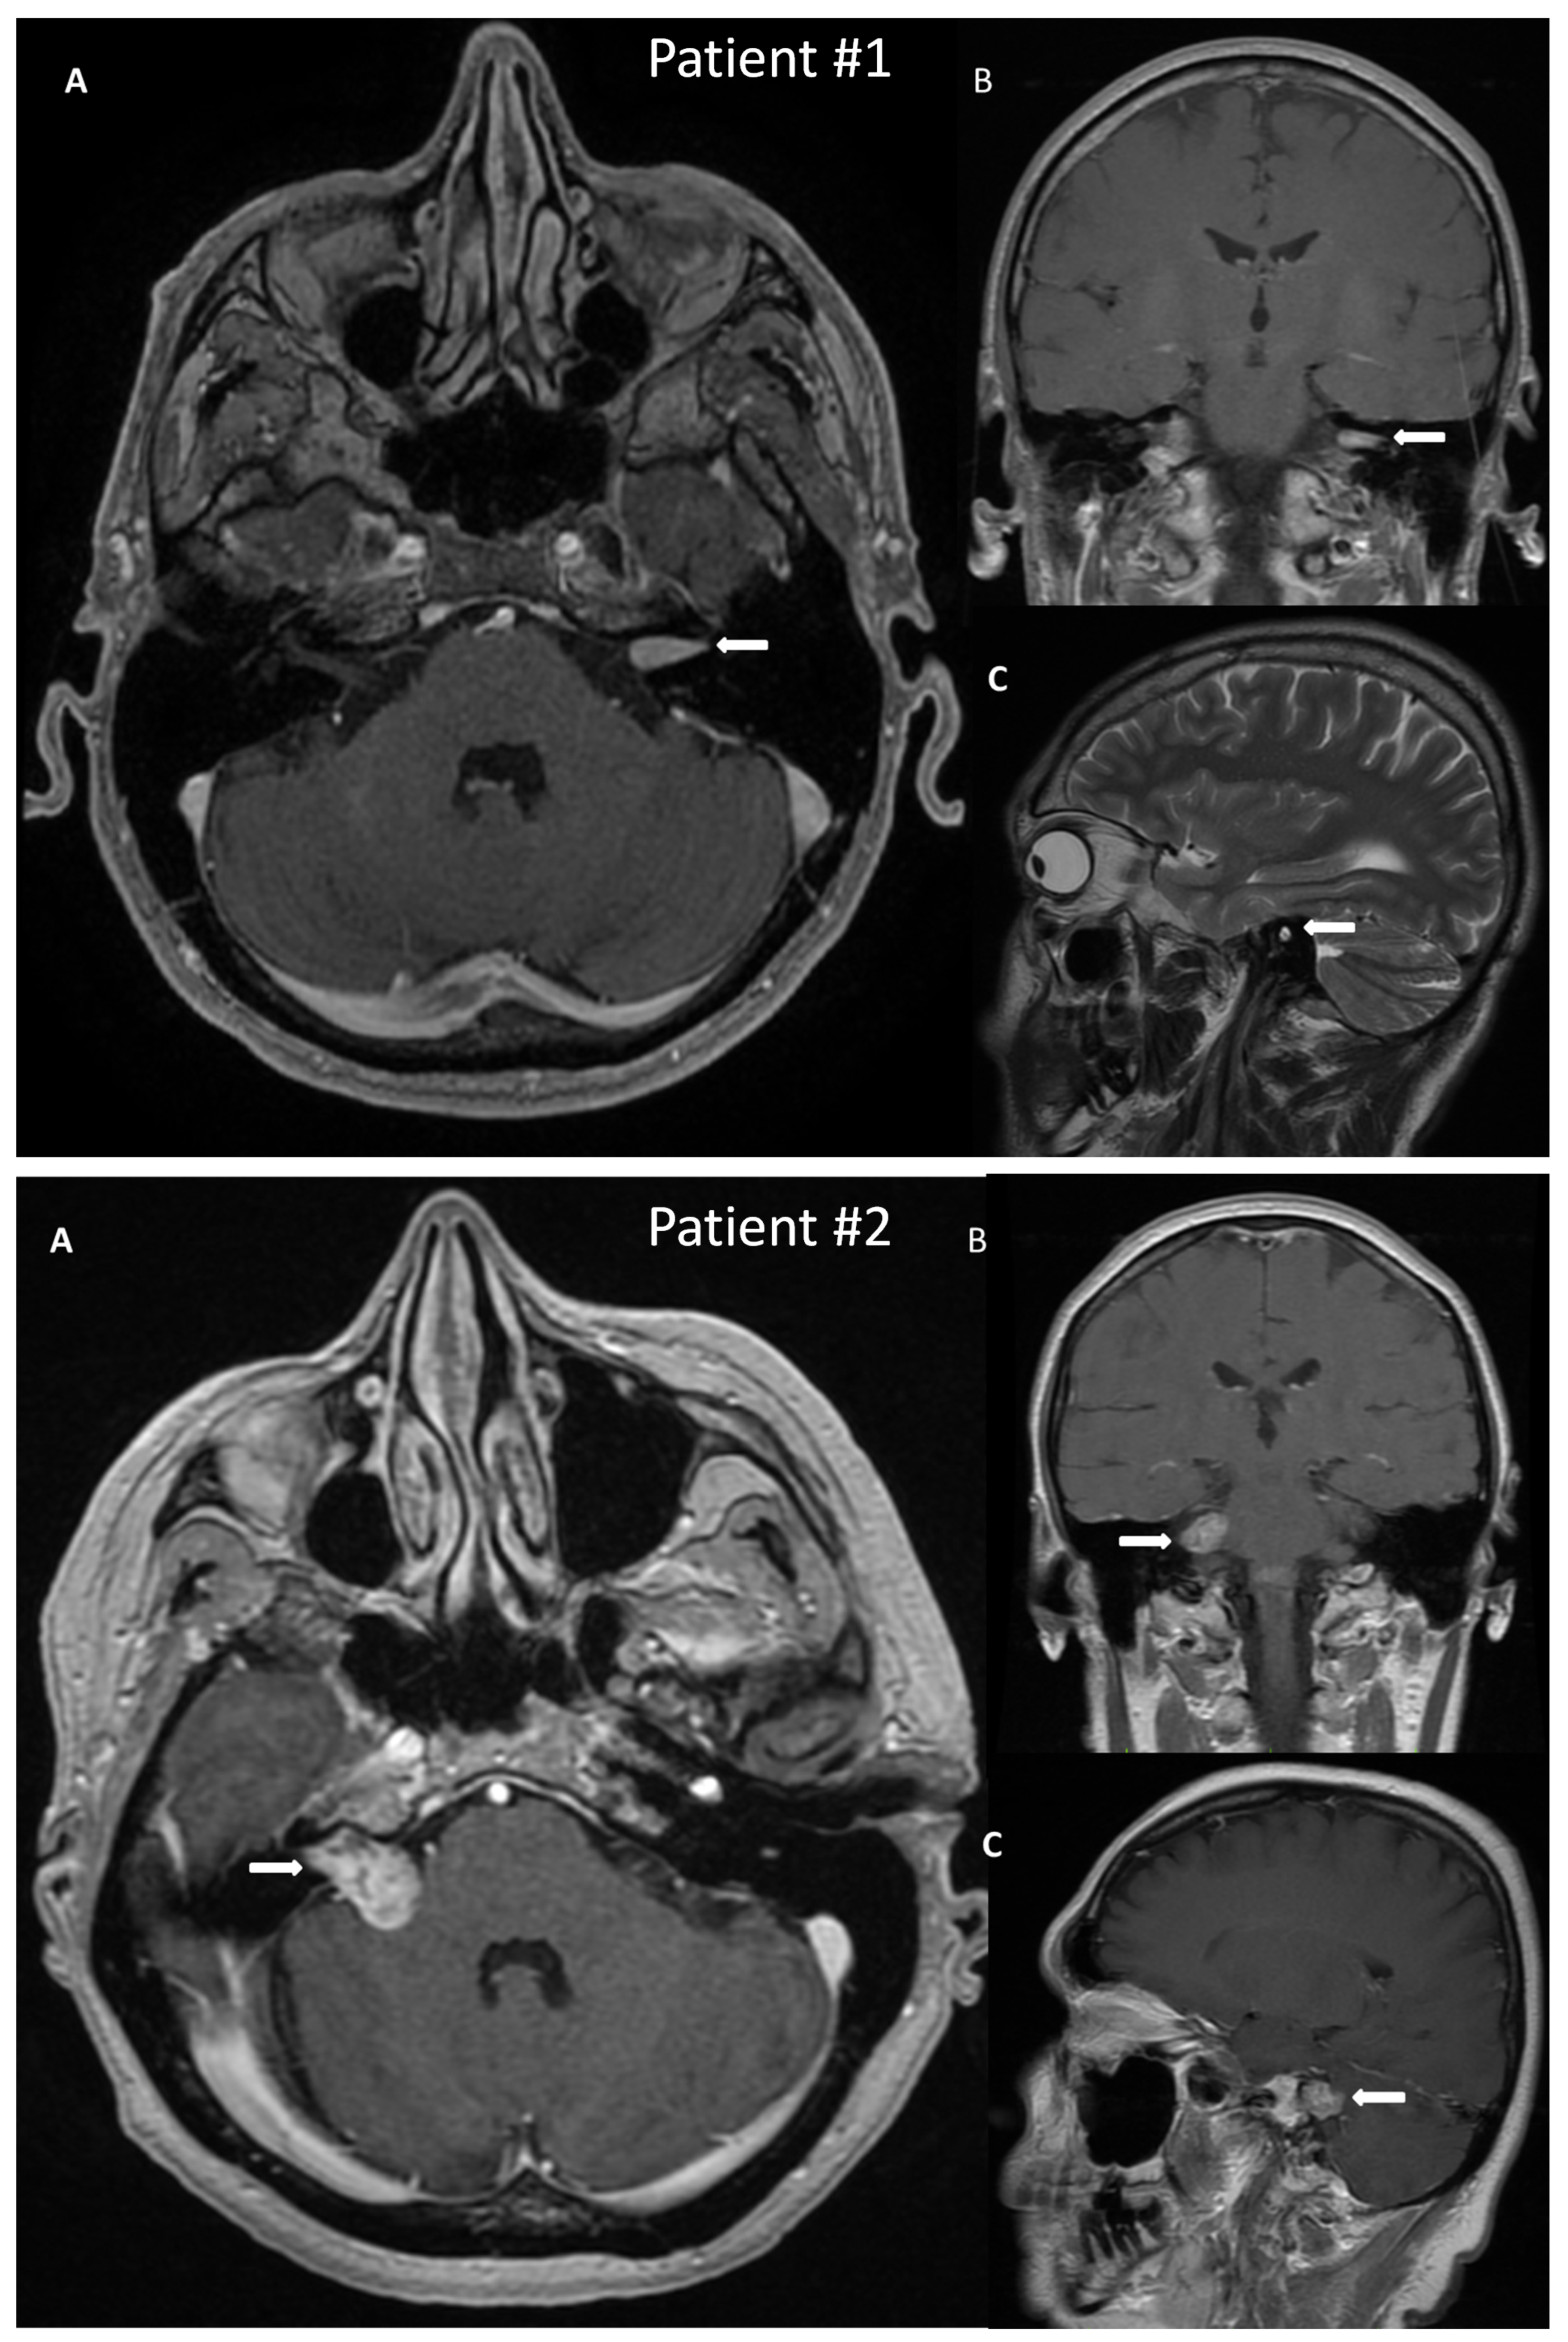

A 50-year-old male patient with a VS on the left side was admitted to the hospital for surgical treatment. On admission, the patient reported progressive hearing deterioration and a feeling of fullness in the left ear lasting many years. In addition, seven months before hospitalization, the patient experienced a single episode of vertigo accompanied by nausea and vomiting, which caused extensive diagnostic testing. The MRI of the posterior cranial fossa revealed a tumor in the left internal auditory canal of the size 14 × 6 mm, radiologically consistent with a schwannoma, Koos grade 1 (Figure 2). Preoperative facial nerve function bilaterally was assessed as I in the H-B scale. The patient did not suffer from any comorbidities.

Figure 2.

Post-gadolinium T1 magnetic resonance images of vestibular schwannoma in Patient #1, tumor located in the left internal auditory canal; and in Patient #2, tumor located in the right internal auditory canal protruding to the right cerebellopontine angle. The tumors are marked with arrows. (A)—axial, (B)—coronal, (C)—sagittal scans.

A 54-year-old female with a VS on the right side was admitted for surgical treatment. On admission, the patient reported progressive hearing loss with a periodic feeling of fullness, congestion in the right ear, and fluctuating balance disorders in the form of ground instability. In addition, she reported incidental pain in the right temporal region. The onset of symptoms was about 18 months before hospitalization. The MRI with contrast revealed a tumor of 20 × 14 mm size, with features of a VS, located in the right cerebellopontine angle and the right internal auditory canal, Koos grade 3 (Figure 2). As for comorbidities, the patient suffered from hypercholesterolemia.